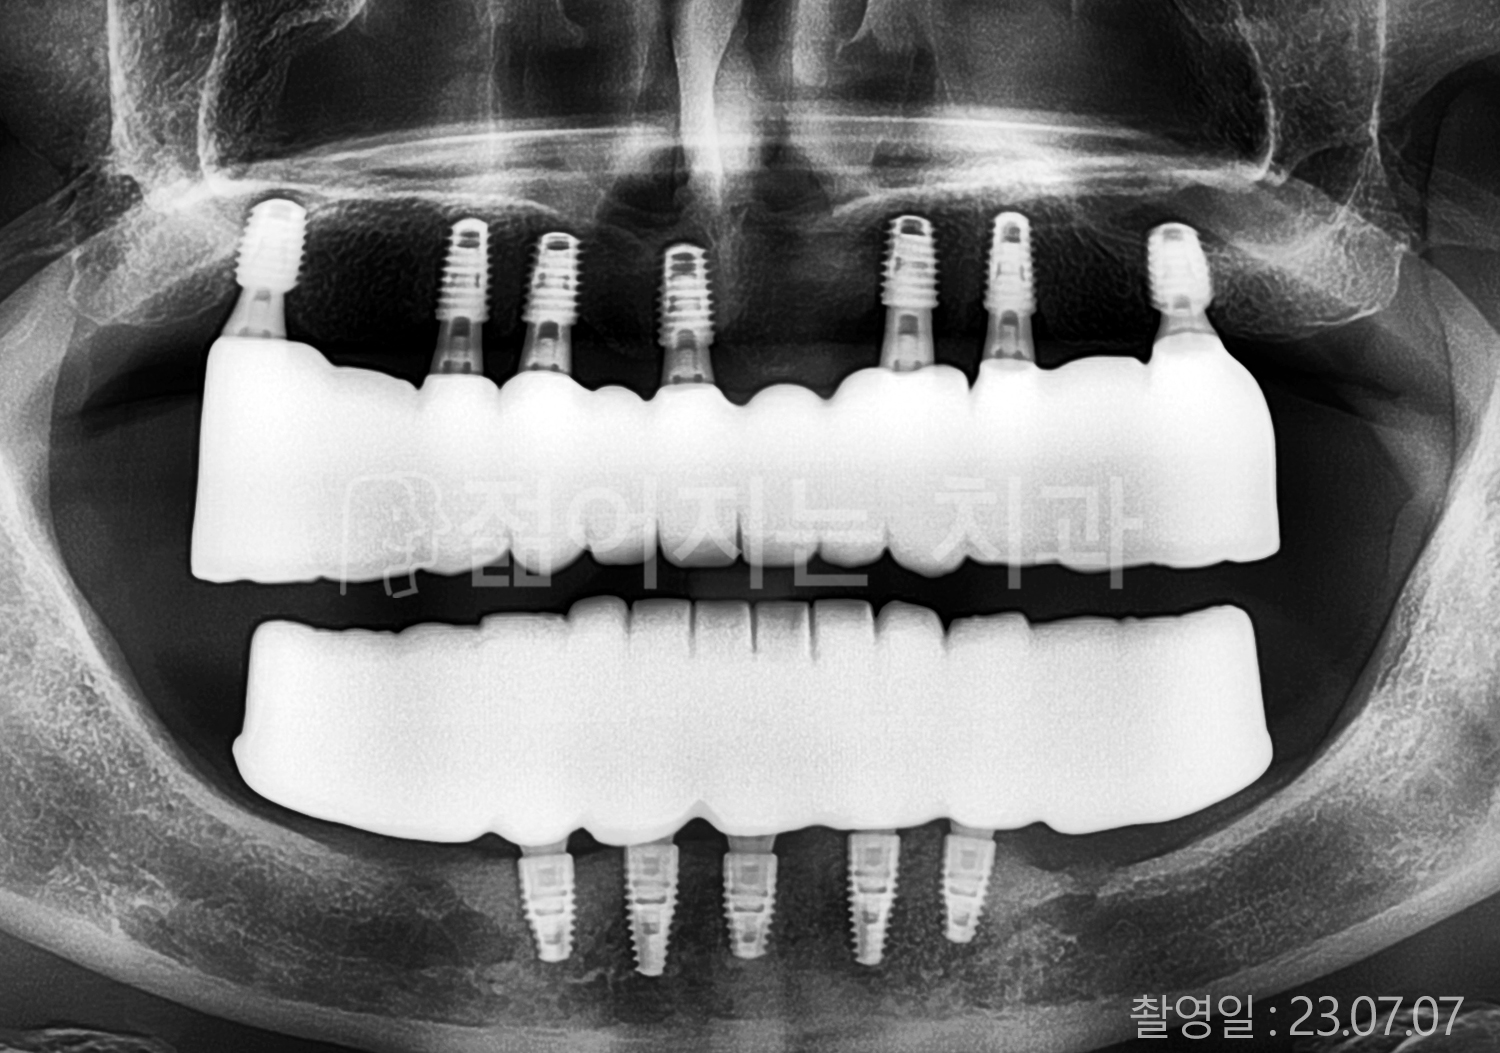

• 40대 전체치아 10개 이상 임플란트

• 50대 전체치아 10개 이상 임플란트

• 50대 고혈압, 당뇨, 고지혈증 전체치아 10개 이상 임플란트